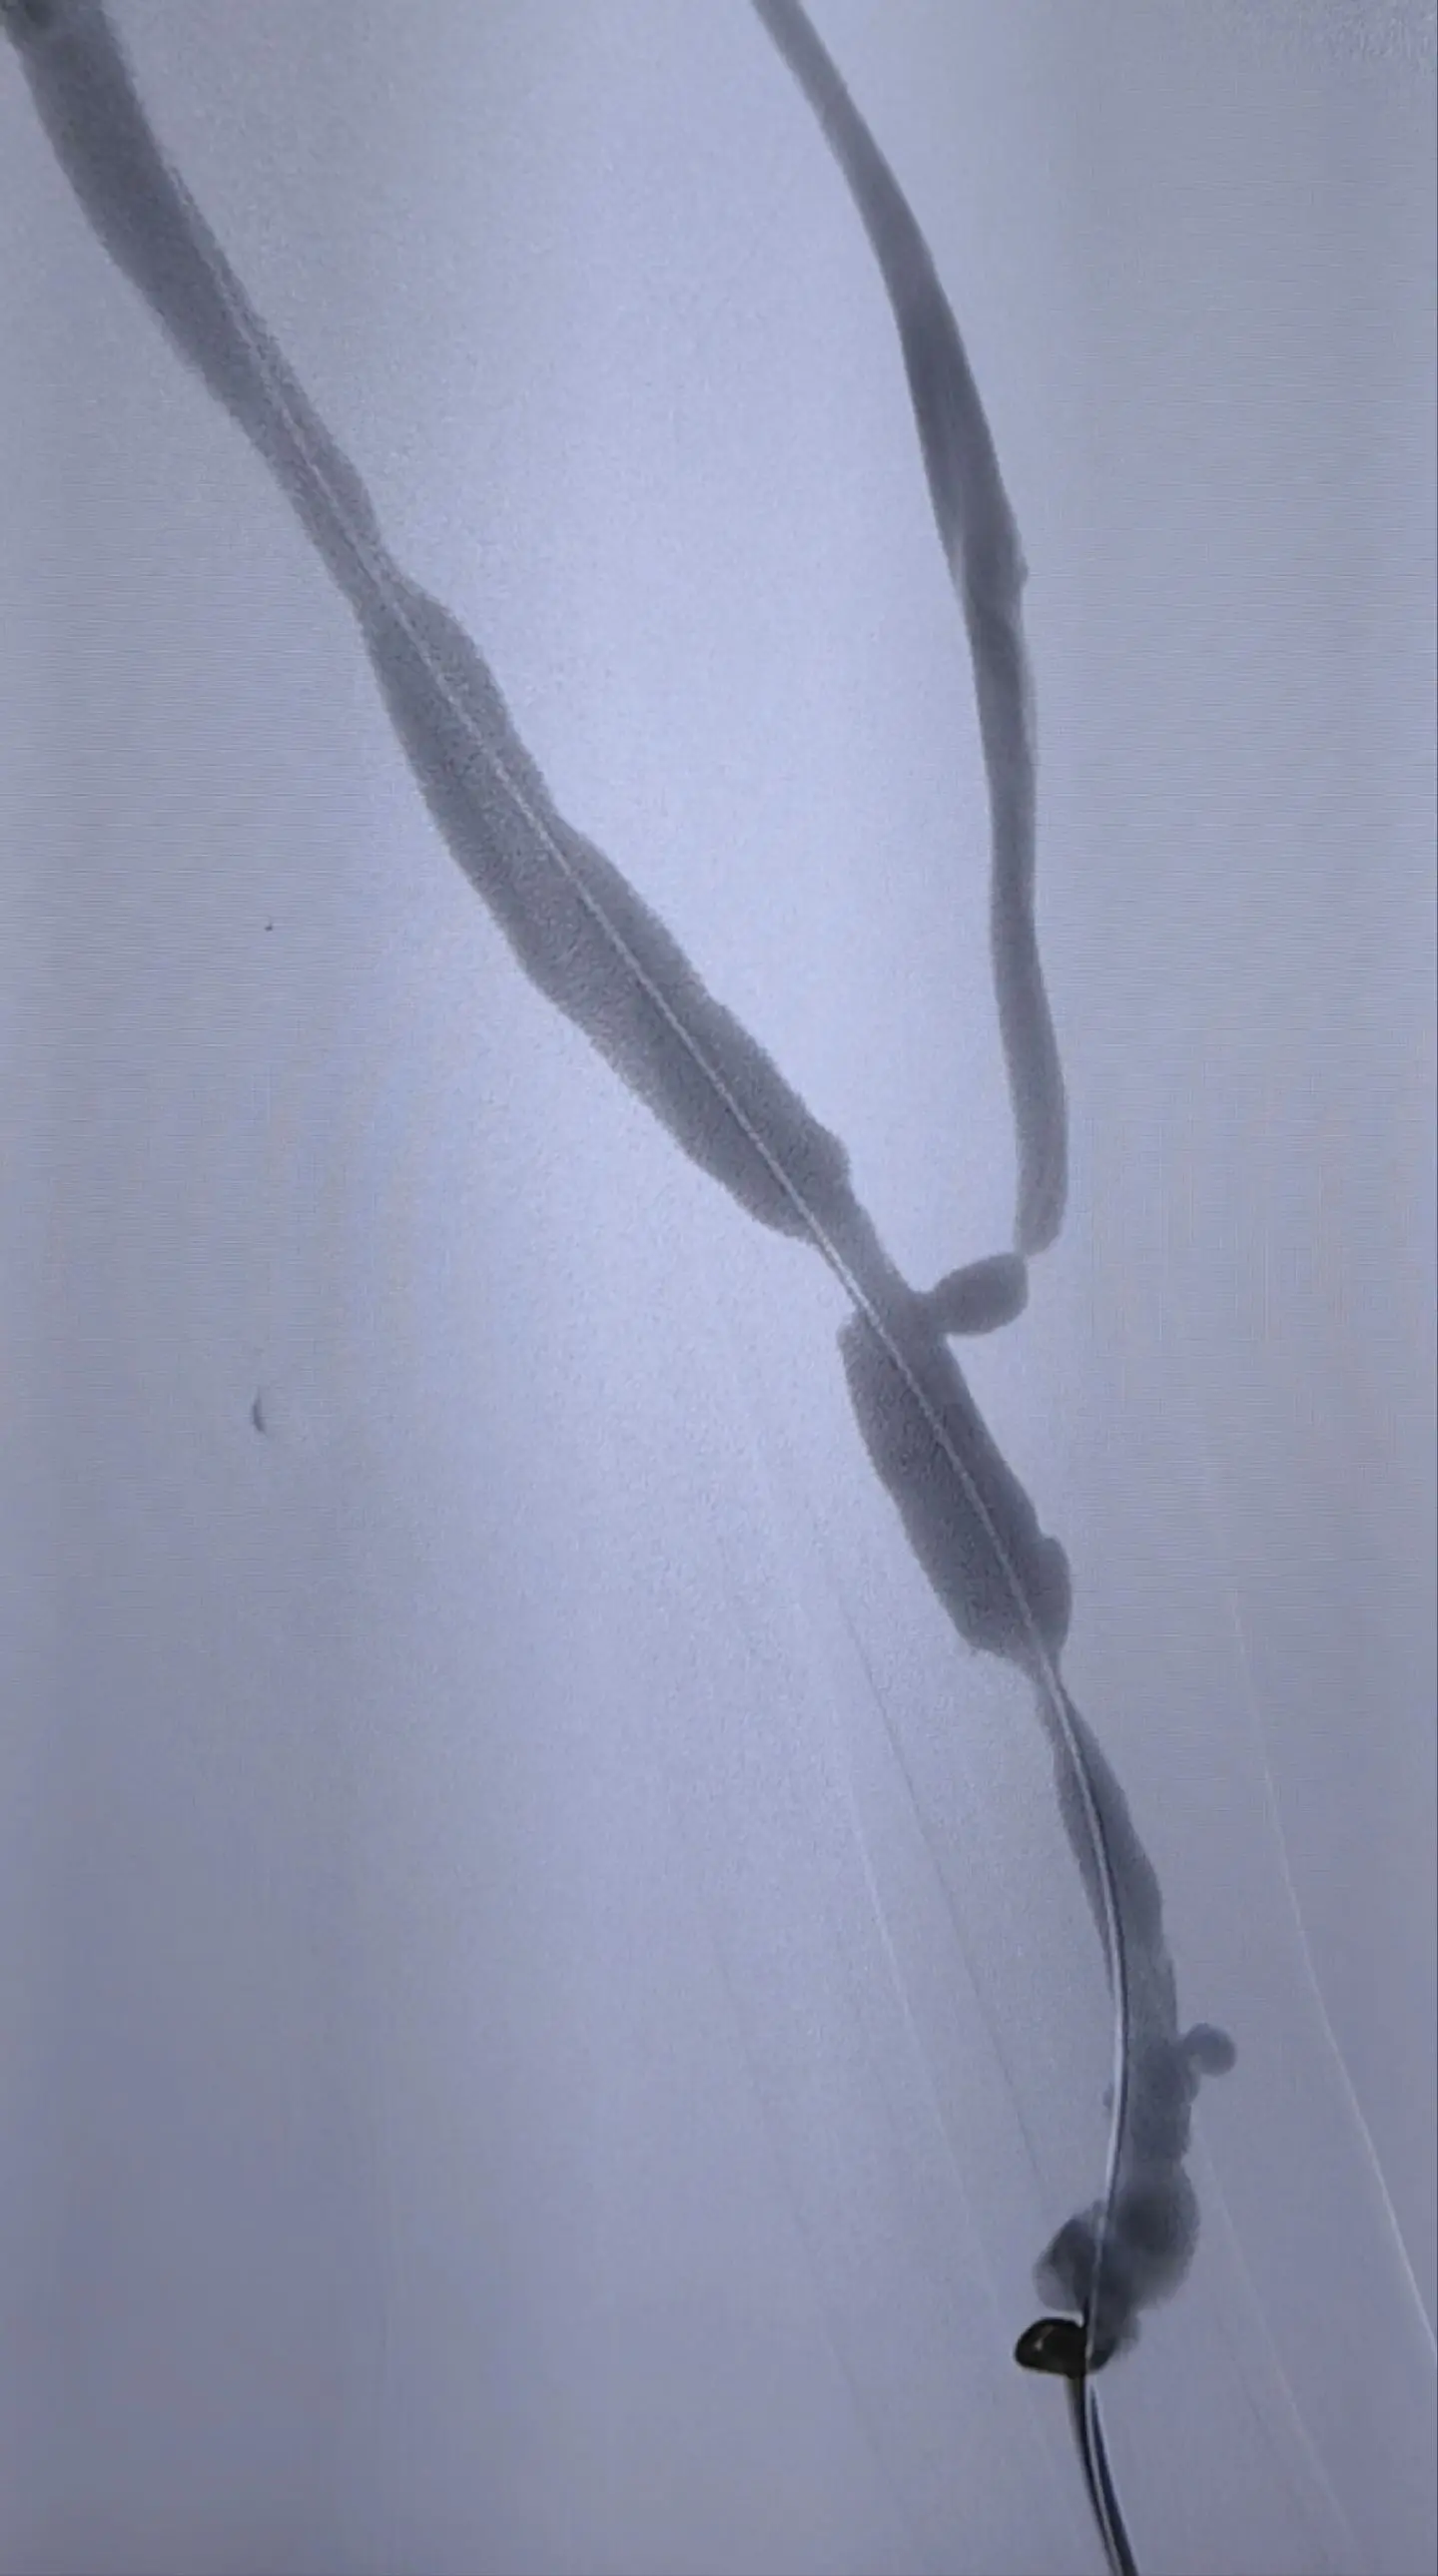

为血透患者维护生命线